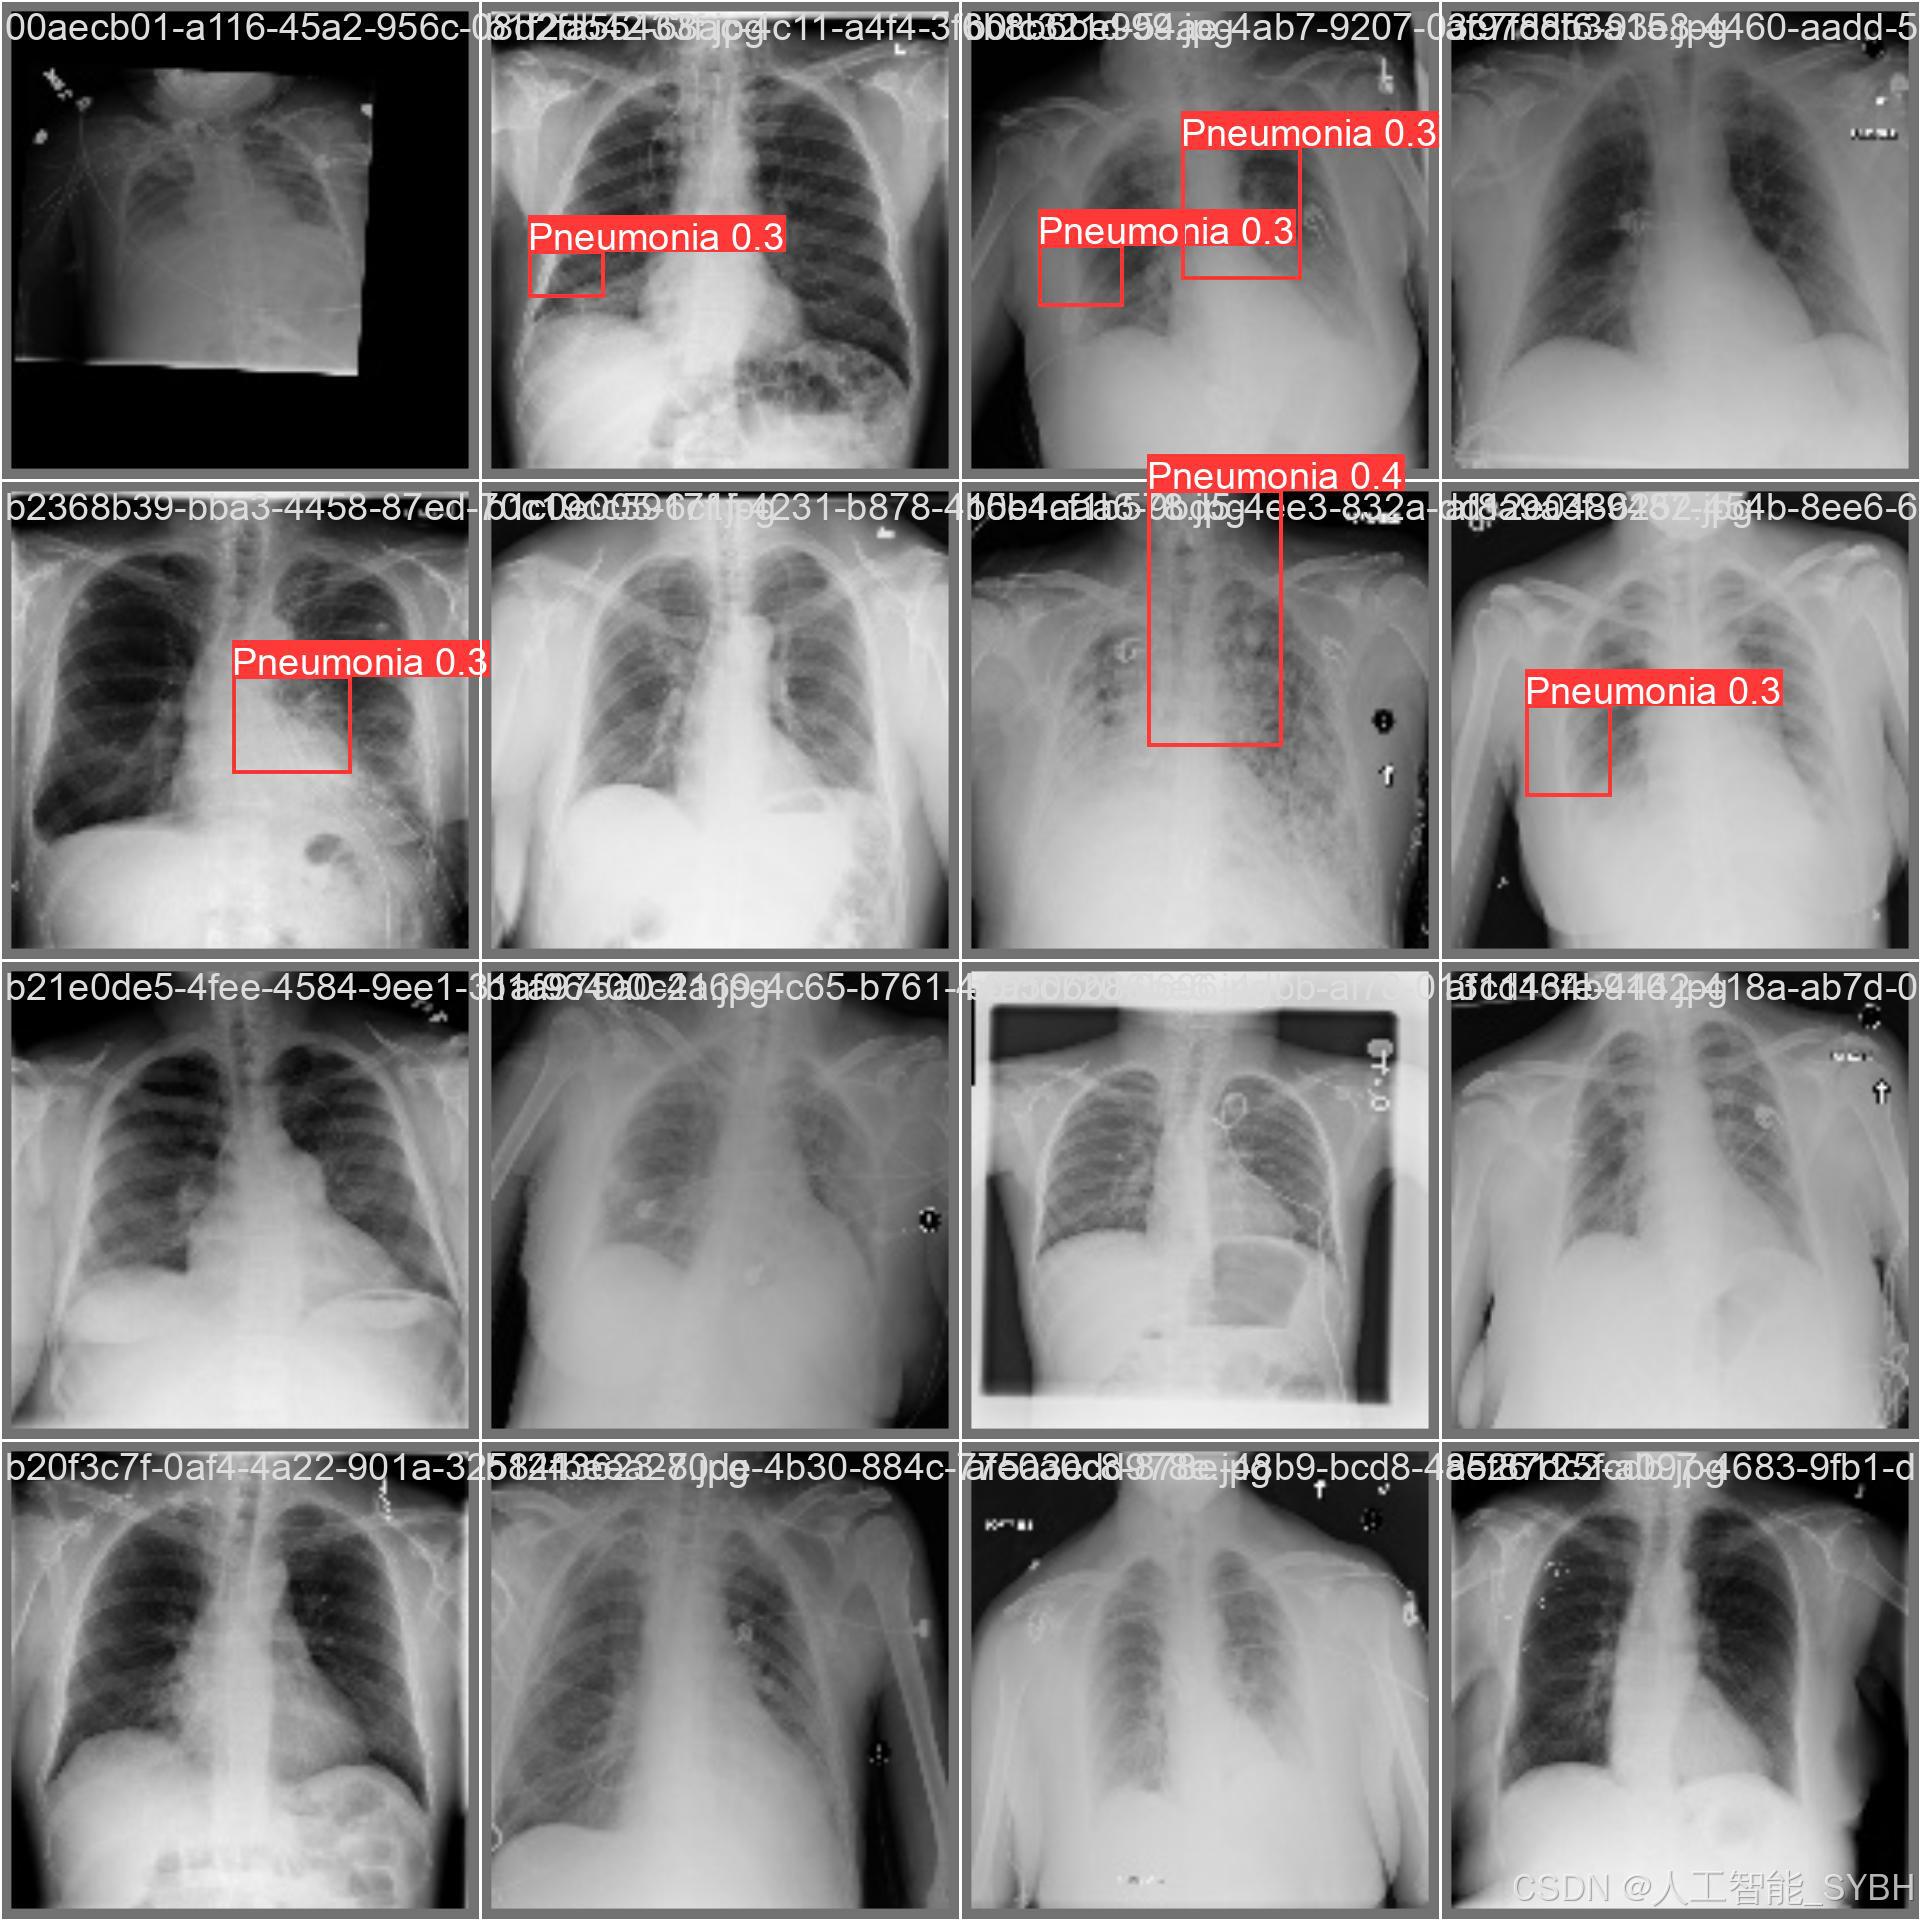

本项目基于YOLOv8深度学习框架,开发了一套高效、准确的肺炎智能检测系统,用于医学影像(如X光或CT扫描)中的肺炎识别。系统针对单类别('Pneumonia'肺炎)进行优化,采用包含3,772张训练图像、539张验证图像和1,078张测试图像的数据集进行训练和评估。该系统能够快速、自动地识别肺炎病变,辅助医生进行诊断,提高医疗检测效率,减少漏诊和误诊风险。

本项目基于YOLOv8深度学习框架,开发了一套高效、准确的肺炎智能检测系统,用于医学影像(如X光或CT扫描)中的肺炎识别。系统针对单类别('Pneumonia'肺炎)进行优化,采用包含3,772张训练图像、539张验证图像和1,078张测试图像的数据集进行训练和评估。该系统能够快速、自动地识别肺炎病变,辅助医生进行诊断,提高医疗检测效率,减少漏诊和误诊风险。

本系统利用计算机视觉和深度学习技术,实现了对肺炎影像的高精度检测,适用于临床辅助诊断、远程医疗筛查和大规模流行病监测等场景。相比传统人工阅片方式,该系统能够大幅缩短诊断时间,提高检测一致性,并降低医疗资源消耗,具有重要的临床应用价值。

数据集通过收集医院中的胸部X光片构建,涵盖了不同年龄段、性别和病情的患者,以确保模型的泛化能力。

每张图像中的肺炎区域均使用边界框(Bounding Box)标注,并标注对应的类别。